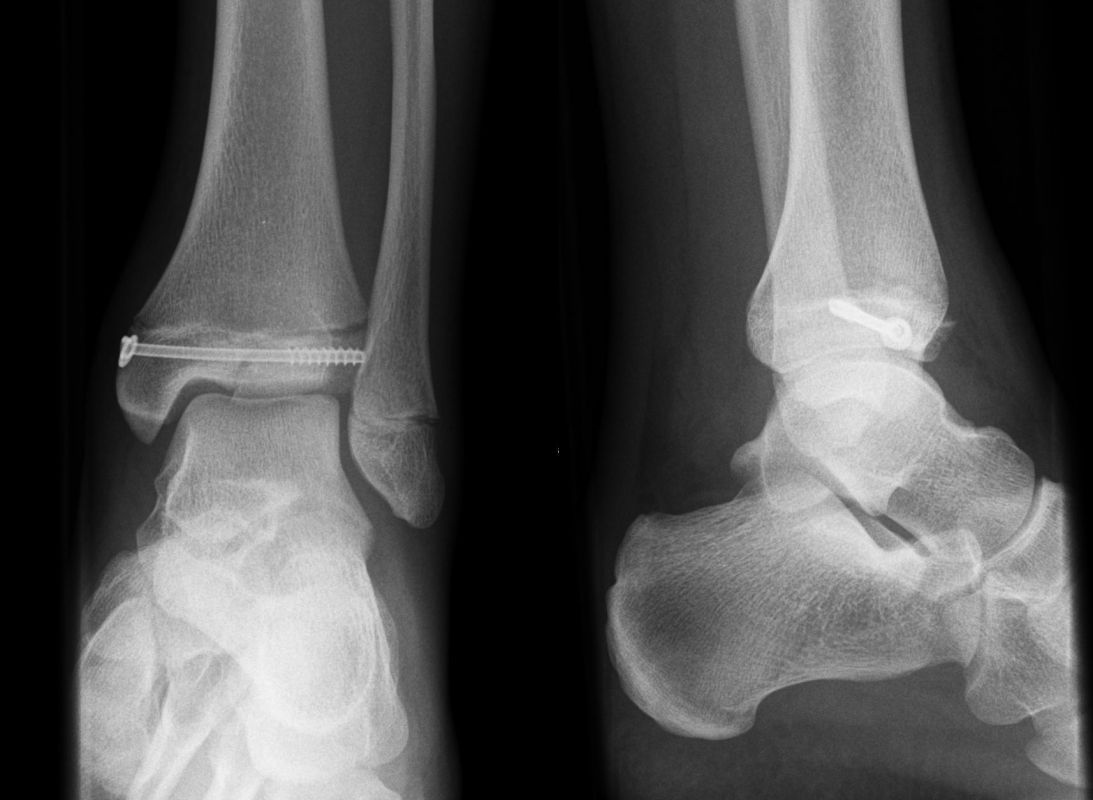

Behandlungsziel ist die exakte Rekonstruktion der Gelenkfläche sowie die Minimierung des Risikos einer späteren Wachstumsstörung. Dislozierte Frakturen werden offen reponiert, die Osteosynthese erfolgt mit einer Kleinfragmentschraube. Finden sich viele kleine Fragmente kann eine K-Draht Osteosynthese durchgeführt werden. Wird der Innenknöchel operiert, kann bei gleichzeitiger hochgradiger lateraler Instabilität eine Rekonstruktion des lateralen Bandapparats durchgeführt werden. Fibula Frakturen stellen sich meist spontan ein, sodass hier keine zusätzliche Osteosynthese notwendig ist.

Nach der Osteosynthese wird die Fraktur für ca. vier Wochen in einem Unterschenkelgips ruhiggestellt. Bei Schmerzfreiheit der Frakturzone erfolgt anschließend eine schmerzadaptierte Belastungssteigerung über weitere zwei Wochen. Sobald unter Alltagsbedingungen Beschwerdefreiheit besteht kann die sportliche Belastung langsam gesteigert werden. Kirschnerdrähte werden 6-8 Wochen postoperativ, Schrauben nach zwölf Wochen entfernt. Es empfiehlt sich klinische und radiologische Kontrollen im Abstand von 6 Monaten bis zum Wachstumsabschluss durchzuführen, um ein mögliches Fehlwachstum frühzeitig zu erkennen.